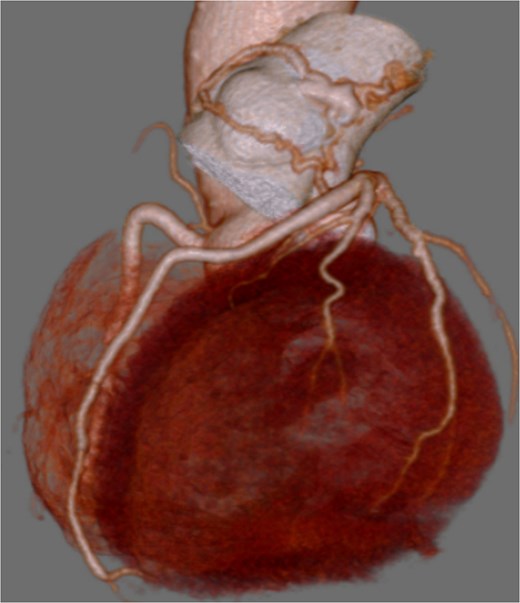

A 73-year-old male presented to his primary hospital with complaints of chest pain. Examination revealed a coronary artery-pulmonary artery fistula and 75% stenosis of the RCA (Figs 1 and 2) with a resting full-cycle ratio (RFR) of 1.0. However, myocardial scintigraphy was negative for ischemia and electrocardiogram (CAG) at rest showed no ST changes (Fig. 3). An exercise resting electrocardiogram (ECG) showed diffuse ST depression, raising suspicion of ischemia due to coronary steal (Fig. 4). Consequently, the patient was referred to our department.

Preoperative coronary CT showing coronary artery-pulmonary artery fistula.